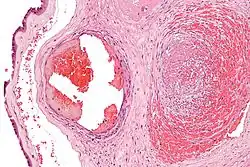

It can be diagnosed by histomorphologic examination of the placenta and is characterized by fetal vessel thrombosis and clustered fibrotic chorionic villi without blood vessels.

Very high mag.

Very high mag.